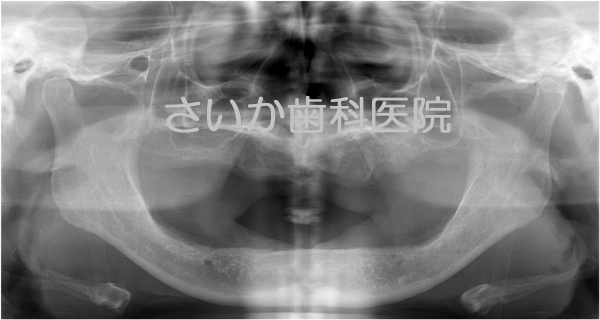

総入れ歯の患者様です。下の入れ歯が安定せず,食事に不自由であるため,インプラント治療を選択しました。

このケースは事前に撮影したCT画像をコンピュータ解析し,歯ぐきを切らずにインプラントを埋め込む方法です(当院の患者様ですが,当院で初めてのケースでしたので奈良県五條市にある中谷歯科医院の堀内克啓先生にご協力いただきました)。

CT解析画像